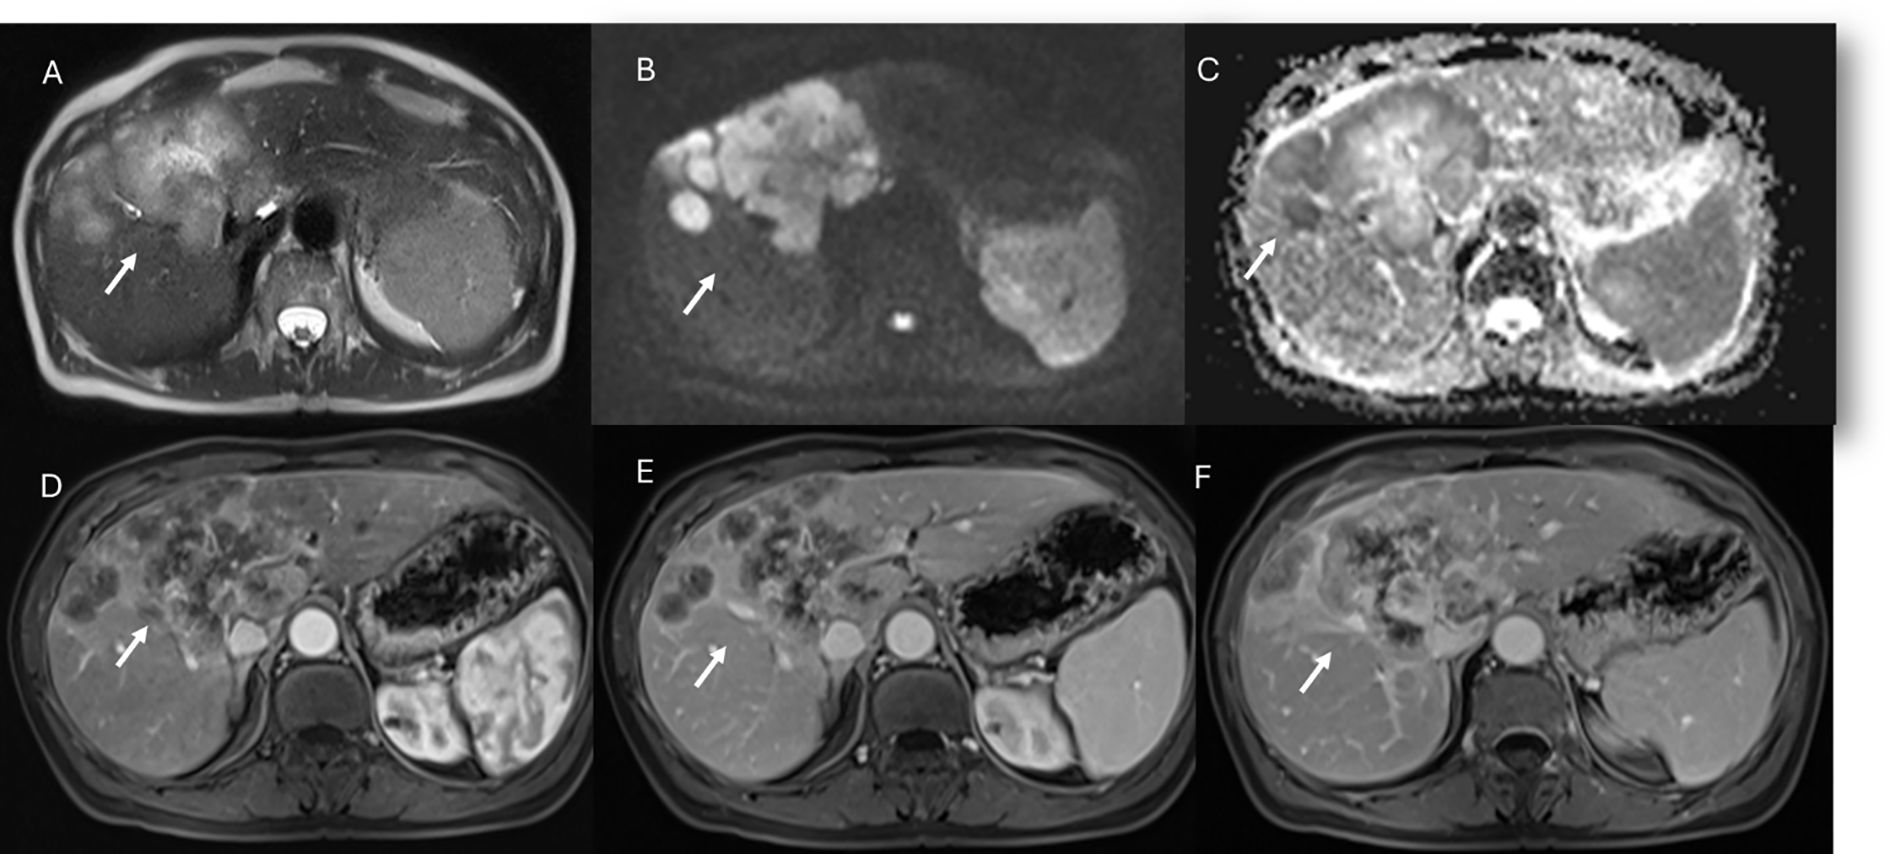

Figure 2. MRI assessment of non-mucinous colorectal liver metastases (arrows). In (A) (T2-W sequence, axial plane), the lesion (arrow) shows hyperintense signal with restricted diffusion on b = 880 s/mm² (B) and targetoid appearance on ADC map (C). After non-specific contrast agent, rim enhancement is seen in the arterial phase (D, T1-W, axial), with peripheral enhancement in the portal (E) and late phases (F) showing targetoid appearance from central necrosis.

Figure 3. MRI assessment of mucinous colorectal liver metastases (arrows). In (A) (T1-W sequence, axial plane), the lesion (arrow) shows hypointense signal, with very high signal on T2-W FS sequence (B) and restricted diffusion on b = 880 s/mm² (C). After non-specific contrast agent, rim enhancement is seen in the arterial phase (D, T1-W, axial), with progressive enhancement in the portal (E) and late phases (F).